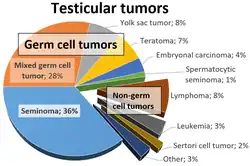

A seminoma is a germ cell tumor of the testicle or, more rarely, the mediastinum or other extra-gonadal locations. It is a malignant neoplasm and is one of the most treatable and curable cancers, with a survival rate above 95% if discovered in early stages.[3]

Testicular seminoma originates in the germinal epithelium of the seminiferous tubules.[4] About half of germ cell tumors of the testicles are seminomas.[5] Treatment usually requires removal of one testicle. However, fertility is not usually affected. All other sexual functions will remain intact.